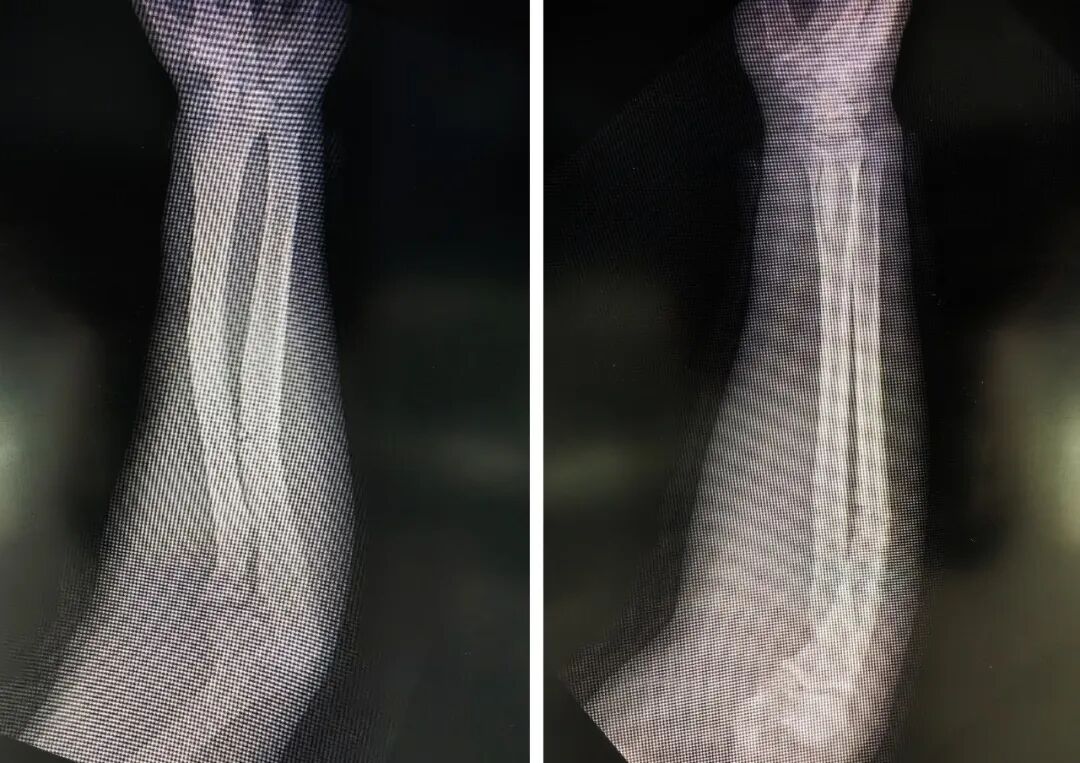

患者,男,61岁,因“前臂严重挤压伤”急诊入院。右前臂肿胀畸形、活动受限,经影像学检查确诊为“尺桡骨双骨折,伴随软组织严重损伤”。若治疗不当,极易引发骨筋膜室综合征、骨折不愈合等严重并发症,严重影响肢体功能。

手术在C型臂X光机精准透视下开展,手术团队严格遵循微创操作规范,通过手法闭合复位,将带锁髓内钉精准植入尺桡骨髓腔,交锁锁钉固定,实现骨折端的稳定复位与加压固定。整个手术过程顺利,术中出血量少,患者生命体征平稳。术后,医护团队在加速康复外科(ERAS)理念指导下,为患者制定个性化康复计划,指导其逐步开展肢体功能锻炼。术后,患者前臂肿胀明显消退,软组织条件明显改善,疼痛症状显著缓解,恢复状况远超预期。

术前